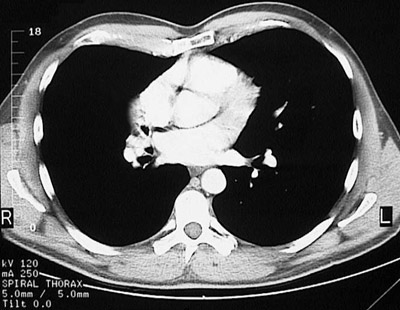

[T8] This is a normal chest CT scan demonstrating the right lung and left lung and pectoralis major muscle and right atrium and pulmonic trunk and left atrium and left ventricle and aortic root and sternum and descending aorta and azygous vein and esophagus and serratus anterior muscle and latissimus dorsi muscle and scapula and rhomboid major muscle and trapezius muscle and sacrospinalis muscle in the upper chest.